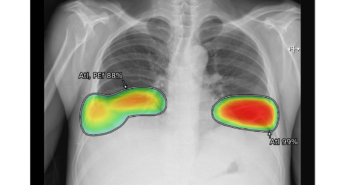

의료 인공지능(AI) 기업 루닛이 군 의료환경 선진화를 위해 해외 파병군 및 격오지 부대 의료기관으로 AI 솔루션 시범도입을 확대한다. 루닛은 최근 과학기술정보통신부 및 정보통신산업진흥원(NIPA)과 'AI융합 의료영상 진료판독시스템 사업’ 4차년도 과업 진행을 위한 협약을 맺고, 흉부 엑스레이 AI 영상분석 솔루션 '루닛 인사이트 CXR'을 공급하기로 협의했다. 루닛은 지난해 3차년도 사업에서 국군의무사령부, 국군수도병원 등 육·해·공 군 의료기관에 루닛 인사이트 CXR을 시범도입해 우수한 평가를 받으며 이번 사업 추진의 교두보를 마련했다. 이를 바탕으로 올해 4차년도 사업에서는 국내 군 병원 외에 해외 군 병원 및 한국 파병부대 등으로 솔루션 제공 범위를 확대할 예정이다. 특히, 해군 선박 등 의료 인프라가 취약한 격오지 부대의 의료환경 개선에 더욱 힘쓸 예정이다. 이를 위해 휴대용 엑스레이 촬영장비와 연동된 맞춤형 AI 솔루션을 개발하고 안정적 활용 체계를 구축하는 등 접근성을 크게 높일 방침이다. 서범석 루닛 대표는 "루닛은 정부의 인공지능 융합(AI+X) 사업 참여를 통해 의료 AI가 군 병원 진료 효율성을 향상시키고 양질의 의료 서비스 제공에 기여할 수 있음을 입증해오고 있다"며 "올해는 국내에서 입증된 루닛의 군의료 AI서비스가 해외 군 병원 및 파병부대에 도입되는 첫 해다. 향후에는 군 의료기관뿐 아니라 전국 보건소 등을 대상으로 하는 의료AI 서비스 확산과 공공의료 인프라 강화에도 더욱 박차를 가할 것"이라고 말했다. 관련 기사 더보기 https://www.venturesquare.net/880545